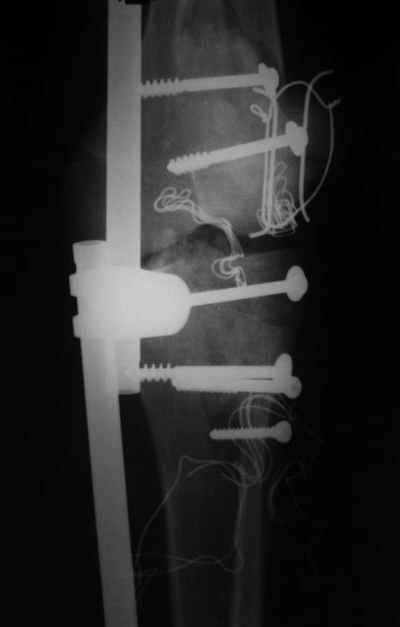

№4 снимок через два дня после операции, супракондилярный перелом, при поступлении конечность была холодная и без пульса, подозрение на повреждение сосудов, сделана ABI (ankle-brachial index) в приемном отделении, индекс меньше 1 к 0.9 в норме 1 к 1.1, срочная ангиография в операционной после Ex-Fix, по два стержня в сегменте наложен в течение 20 мин, повреждение подколенной артерии, ушивание сосудистым хирургом через медиальный доступ в дистальном отделе бедра и двухразрезная профилактическая фацсиотомия, перкутанная фиксация каннюлированными шурупами несмещенного перелома шейки бедра и дополнительные стержни в фиксаторе для жесткости.

Я предупреждал, что ничего сверхъестественного. Каюсь, что одна из спиц прошла несколько дальше, чем нужно было, но главное - перелом стабилизирован и больной работает суставом в полном объёме, несмотря на представленную раннее травму коленного сустава.